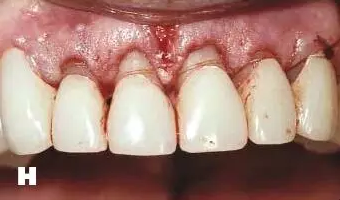

牙周炎發(fā)展到一定階段時(shí),僅采用基礎(chǔ)治療難以取得較好療效,必須通過(guò)適時(shí)而合宜的手術(shù)治療挽救患牙,才能保持牙周組織健康,延長(zhǎng)患牙在口腔內(nèi)的壽命,維持牙列的完整性,促進(jìn)全身健康。其手段包括齦下刮治、根面平整、牙周翻瓣術(shù)、牙齦切除術(shù)、牙周夾板固定術(shù)等。

1、美容手術(shù):針對(duì)牙齦增生、影響美觀效果的患者,進(jìn)行牙齦的美容切除手術(shù),修整牙齦的形態(tài),恢復(fù)美容效果。